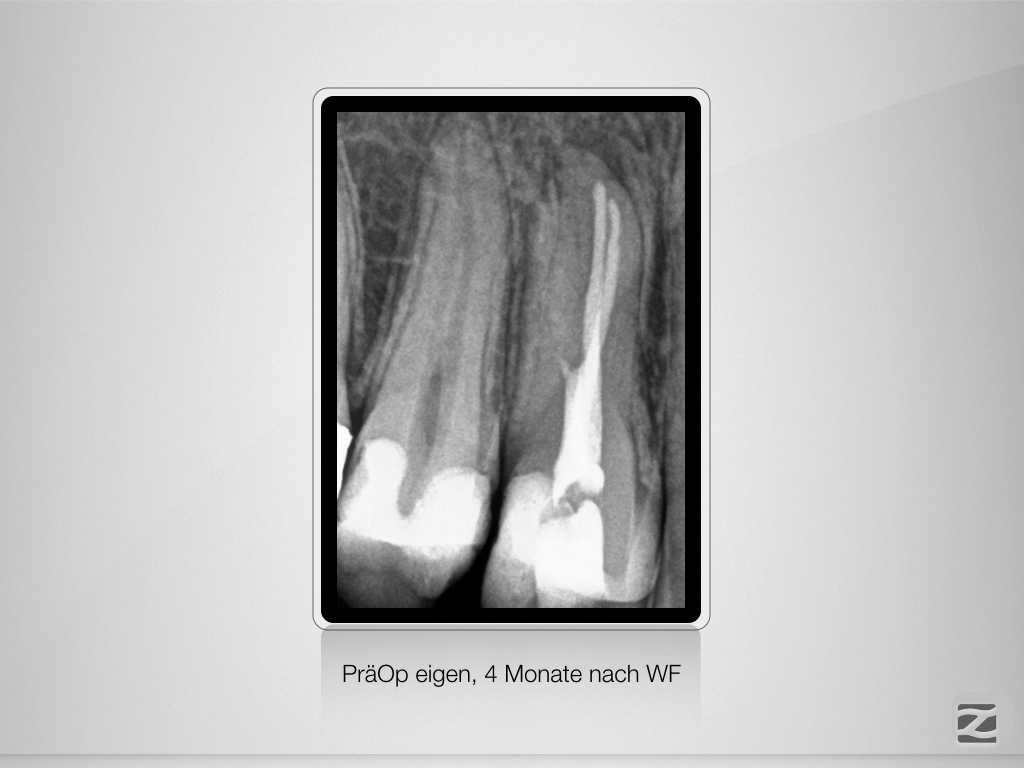

Schöner Dreier